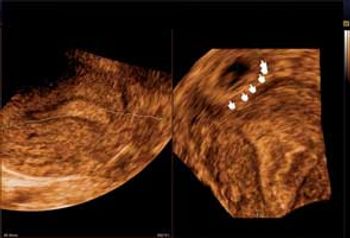

New research shows that symptoms exist in even early-stage ovarian cancer, disproving the myth that it's a "silent killer." Barbara Goff, MD, presents the latest in symptom research, tips on what physicians should be looking for, and what's on the horizon for ovarian cancer screening.